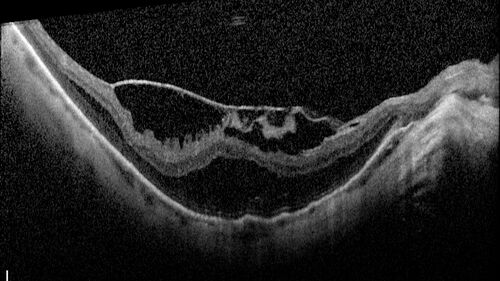

Stable Myopic Tractional Maculopathy

73 year old female with mild vision loss from table myopic tractional maculopathy in the left eye